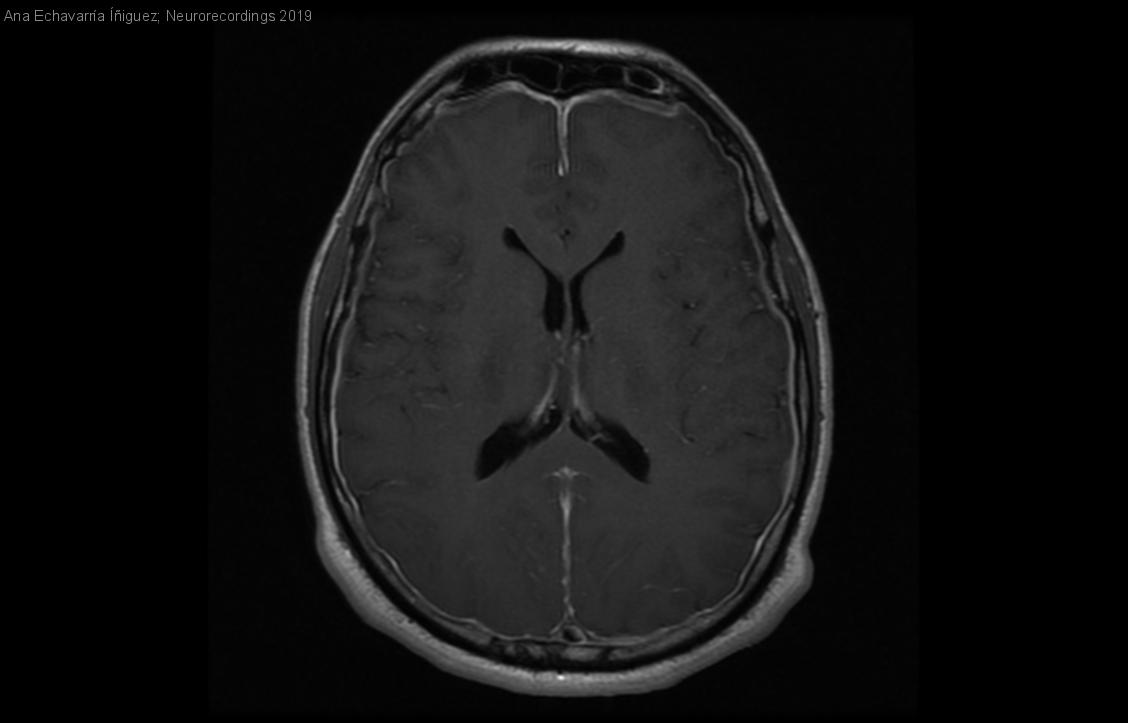

Hombre | 45 años

Diagnóstico final: Hipotensión intracraneal

Resumen del caso

Varón de 45 años sin antecedentes previos de interés que ingresa para estudio de cefalea occipital progresiva y paresia de VI par craneal izquierdo. La cefalea aparece al poco tiempo de iniciar la bipedestación y...